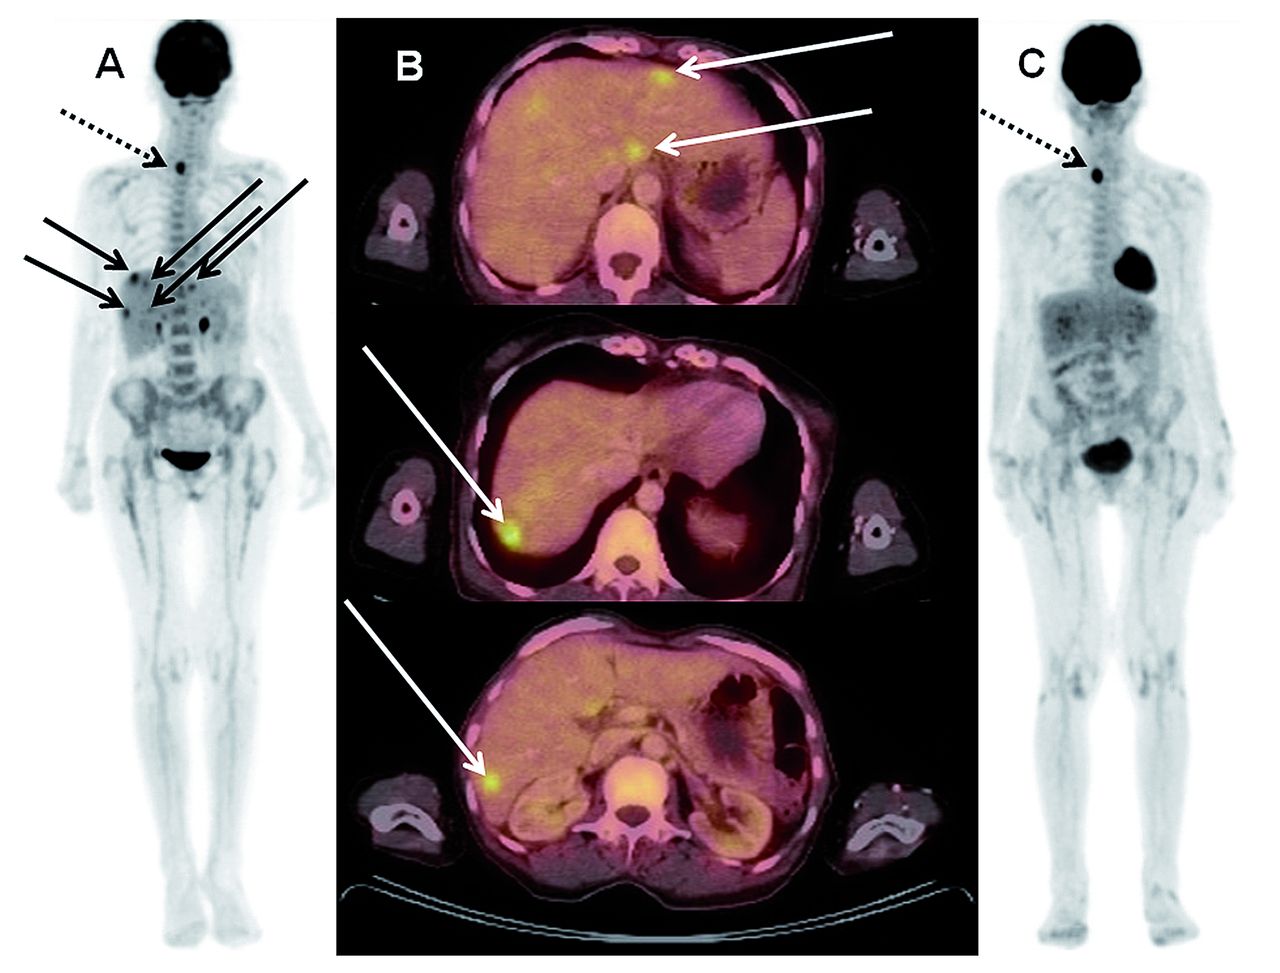

Figure 2.Images of a 69-year old female patient with histologically confirmed extramedullary (EM), bilobular hepatic manifestations of acute myeloid leukemia (AML) (continuous arrows) who underwent intensive induction chemotherapy. (A) Maximum intensity projection (MIP) and (B) three representative slices of the fused multiplanar reconstructions (MPR) of the pre-therapeutic 18Fluorodesoxy-glucose positron emission tomography/computed tomography (18FDG-PET/CT). Maximum standardized uptake value (SUVmax) ranged from 5.2 to 7.4. (C) MIP of the post-therapeutic 18FDG-PET/CT confirming a complete metabolic remission of all hepatic lesions. Note the hypermetabolic focus (SUVmax 8.9) in the right thyroid lobe (dotted arrows, see also (A) at baseline) which does not reflect AML but rather a thyroid adenoma that was still present in the post-therapeutic scan (SUVmax 8.1).

Follow-up 18FDG-PET/CT

Patients with EM diagnosed by FDG-PET/CT underwent a second FDG-PET/CT scan at confirmation of CR or, at the latest, until day 60 after initiation of therapy in case no CR was achieved. A total of 14 of 21 patients with EM AML as per baseline FDG-PET/CT at diagnosis underwent a second FDG-PET/CT. The remaining patients did not undergo a second FDG-PET/CT because of severe disease and intensive care treatment (n=3), mental distress (n=1), palliative care in a hospice (n=1), and withdrawal of study consent for the second FDG-PET/CT (n=2). When we analyzed only the follow upFDG-PET/CT of those patients who were FDG-PET/CT positive and had a positive confirmatory biopsy (n=10 patients), 60% of these patients (n=6) were still positive for EM AML as diagnosed per the second FDG-PET/CT. Exemplary FDG-PET/CT imaging of a responding and a non-responding patient (who both underwent intensive induction chemotherapy) is available in Figures 2C and 3C-E. Interestingly, of the six patients who still had EM AML (as per FDG-PET/CT imaging) at the time of their second FDG-PET/CT, four patients with EM AML and AML bone marrow infiltration at diagnosis were in CR as determined by bone marrow cytomorphology at the time of second FDG-PET/CT. Of those four patients who still had EM AML in their second FDG-PET/CT, but who were in CR as per bone marrow cytomorphology, three patients subsequently relapsed. The other two (of the six patients with persistent metabolic disease) had isolated EM AML as per FDG-PET/CT: one patient had unchanged EM AML manifestations in the second FDG-PET/CT, while the other had a progression of EM AML manifestations in the second FDG-PET/CT. The metabolic and numerical dynamics of EM AML manifestations in patients with histologically confirmed EM AML from baseline to follow up FDG-PET/CT are shown in Online Supplementary Figure 1A and B.